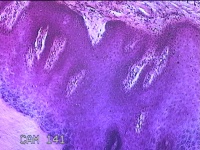

右侧足底结节

性别

男

年龄

41岁

临床诊断

鸡眼和胼胝

一般病史

发现右侧足底结节伴隐痛不适半年余。

标本名称

大体所见

灰白粉红色带皮肤样结节1x0.8x0.3cm一个,表面糜烂,切开结节呈实性,切面灰白粉红色,质硬。

图1